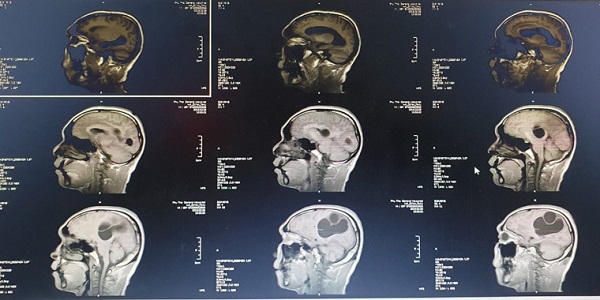

Hình ảnh tổ sán lớn trong não trên hình ảnh phim chụp - Ảnh: Vietnamnet |

Sau khi chụp CT, MRI sọ não, bác sĩ phát hiện một ổ sán khổng lồ ở bán cầu não trái và vùng thái dương đỉnh phải. Phù não đè đẩy đường giữa. Bệnh nhân được chỉ định can thiệp ngoại khoa cấp cứu vào lúc 23h ngày 9/3. Ca mổ kéo dài khoảng 2 tiếng, ổ sán lớn trong não được lấy ra nhờ hỗ trợ của các thiết bị hiện đại như kính hiển vi, máy hút siêu âm...